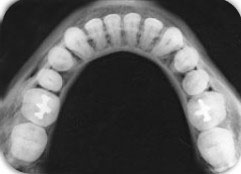

RX. Oclusal superior